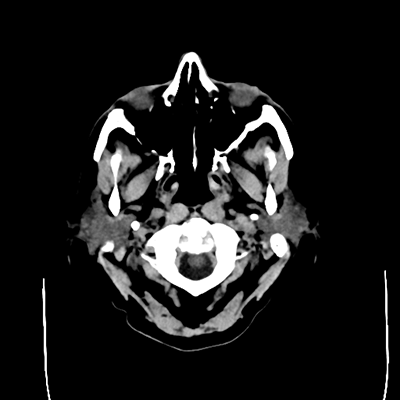

A 71 year-old woman with a history of alcohol use disorder presents to the ED from her subacute rehab facility with gait difficulties and a ground-level fall earlier today. She is found to have an acute-on-chronic left subdural hematoma. On exam, she is mildly somnolent and has 4/5 right upper and lower extremity strength.

NCHCT